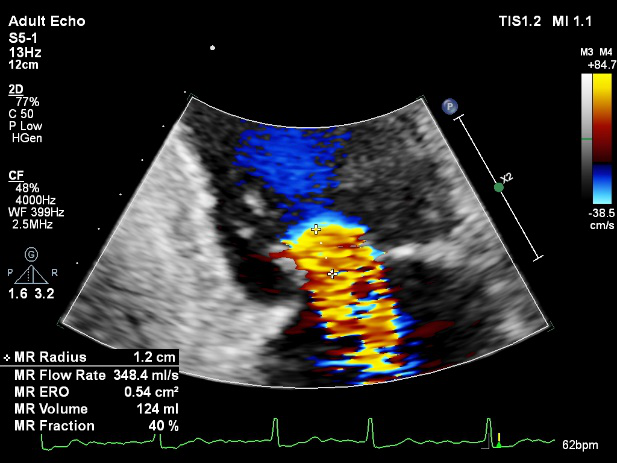

LVOT-color:MR(重度),返流面积11.3cm2

TEE LVOT切面返流量评估

TEE 4-Ch view返流量评估

患者麻醉方式为全麻,建立静脉通路后,穿刺右侧股静脉,预埋ProGlide缝合器,食道超声指导下房间隔穿刺成功,将Superstiff导丝送至左房,应用18F鞘管扩张穿刺部位,沿导丝将导引导管送入左房,MitraClip调整后顺利到达二尖瓣目标位置,在X线及食道超声辅助下,将Mitraclip NTR成形夹精确定位后,成功夹合二尖瓣A2-P2区,超声显示反流明显减少,多切面证实夹合组织充分,肺静脉多普勒波形由反向恢复正常,手术顺利结束,安返普通病房。

3D-color:残余少量返流